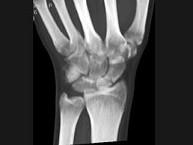

问题 男,21岁,手部不慎摔伤,局部疼痛,结合图像,最可能的诊断是?(?)

选项 A.大多角骨骨折 B.小多角骨骨折 C.三角骨骨折 D.月骨骨折 E.舟状骨骨折

答案 E